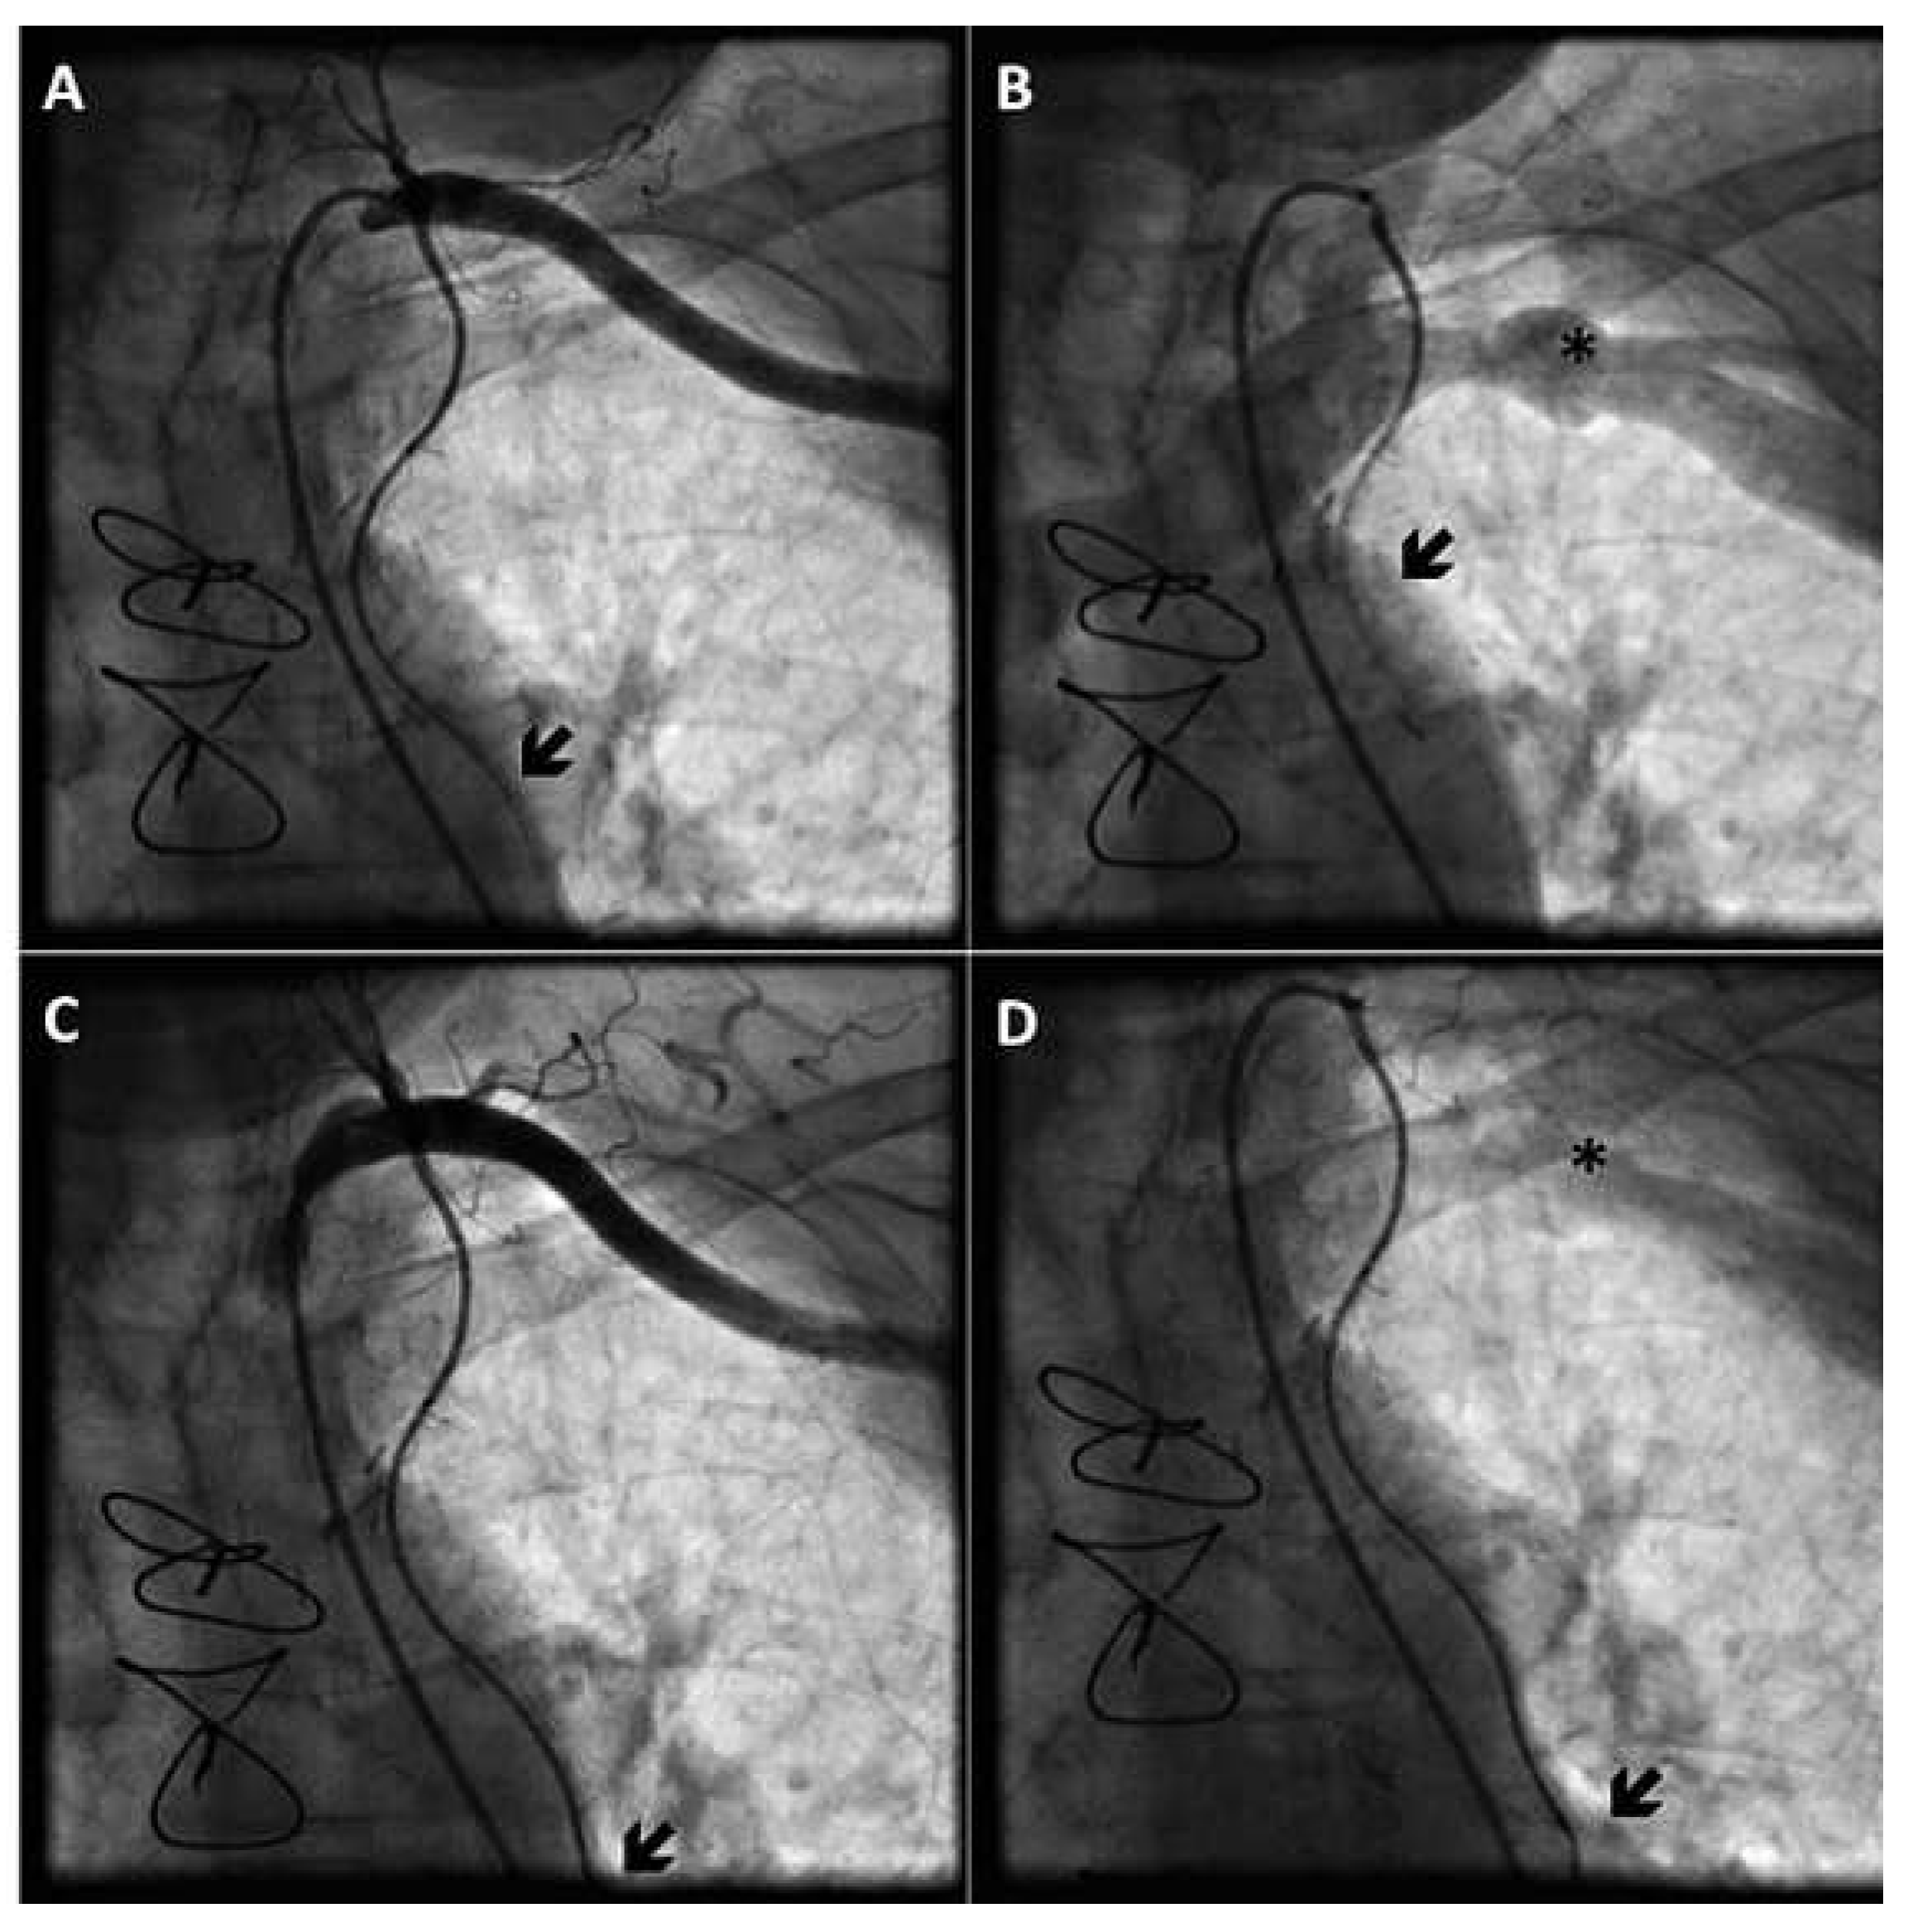

We confirmed the presence of steal due to the ipsilateral AV fistula by occluding the shunt with a pneumatic cuff, which resulted in restoration of antegrade bypass flow during both systole and diastole (Figure 2).

Figure 2. Demonstration of ITA steal due to AV shunt using a pneumatic cuff to occlude the fistula. Deflated cuff: selective injection into the left ITA graft shows an opposition to antegrade flow within the ITA graft (A,B), and a prominent wash-out of contrast medium through the subclavian vein in the late phase (B). Inflated cuff: normal antegrade flow in the ITA graft (C,D), and absence of wash-out of contrast medium through the subclavian vein (D). Black arrows indicate the maximum range of antegrade bypass flow. Black stars indicate the subclavian vein.